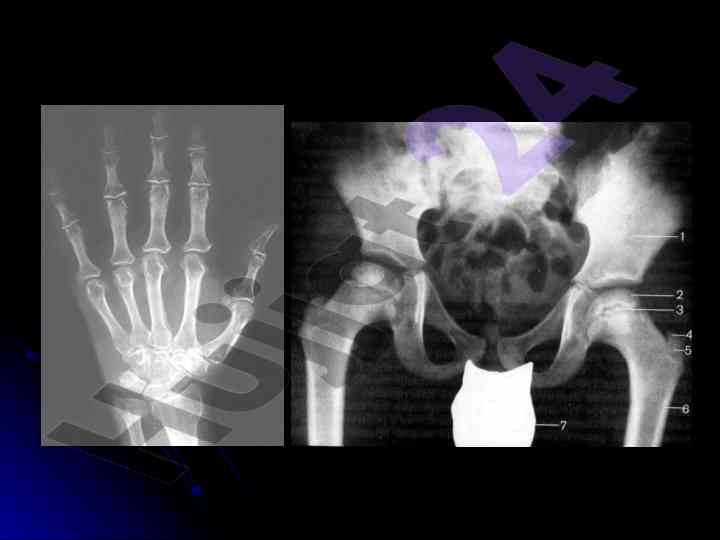

Ushbu mustaqil ishda tayanch-harakat tizimi kasalliklarining nur tashxisi va rentgenografiya orqali suyak minerallanishi holatlari o'rganilgan. Suyak va yumshoq to'qimalar haqida muhim ma'lumotlar taqdim etilgan.